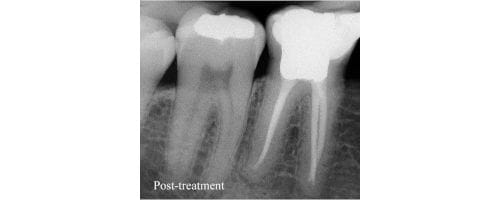

After eradicating the infection from the tooth, a dental crown is placed over the area to protect the natural tooth from further damage. This is the gist of the Root Canal Treatment. Generally, people are less concerned when it comes to a dental treatment. Hence, most patients avoid getting dental treatment done and also feel that dental procedures are very expensive and time-consuming as multiple visits are required. However, Root canal treatment is a very common dental procedure and can be carried out in one sitting.

Conclusion

Sometimes, during the treatment, even the patients give their past dental history to their dentist when it comes to getting a root canal treatment done. Pain management strategies like use of analgesic medications, cold pack application are also used. Root canal therapy is a must tooth saving procedure which we advise to the patients to undergo in order to save their natural tooth as it is beneficial for functional and aesthetic purpose.